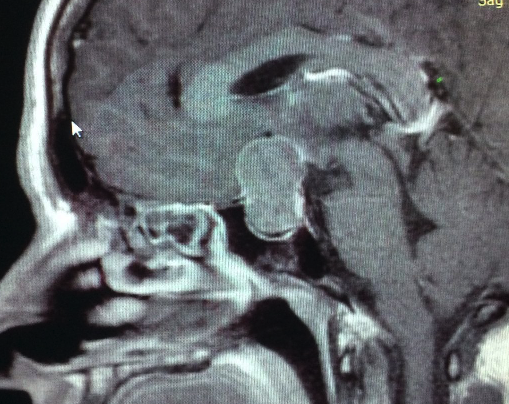

Ver caso clínicoCraneofaringiomas

Los Craneofaringiomas son tumores benignos de la región selar y supraselar derivados de las células epiteliales de la Bolsa de Rathke.